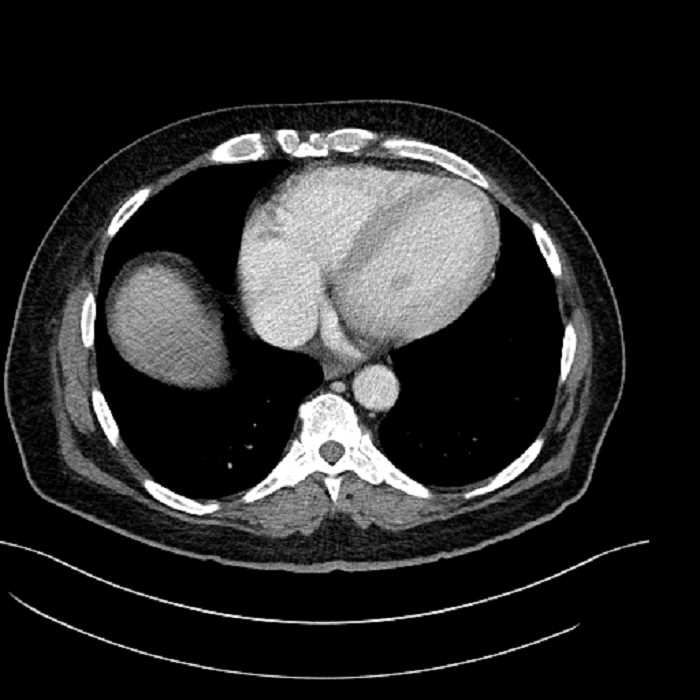

• Lower chest

• Mild cardiomegaly

• Mild dependent atelectasis

Acute sigmoid diverticulitis complicated by a small contained perforation and a large abscess in the right hepatic lobe. Additional small subcapsular abscesses along the anterior margin of the left hepatic lobe.